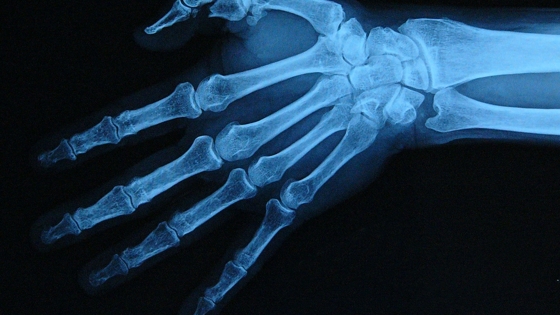

Эпилепсия — психоневрологическое заболевание, которым страдает около 50 миллионов человек во всем мире. Основные препараты при лечении эпилепсии — антиконвульсанты. В их числе карбамазепин, вальпроевая кислота, ламотриджин, леветирацетам, лакосамид и другие. Основная цель терапии — достичь полного прекращения эпилептических приступов с минимальным риском развития побочных эффектов. При этом считается, что прием антиконвульсантов негативно сказывается на минеральном обмене костей, уменьшая в них содержание кальция и фосфора. Это, в свою очередь, может приводить к истончению и «ломкости» костей. Однако в литературе еще мало исследований с надежными данными о том, как связаны прием антиконвульсантов нового поколения и развитие остеопороза.

Состояние испытуемых ученые оценивали с помощью разработанной ими регистрационной карты. В нее вошли обезличенные данные о возрасте, диагнозе, терапии, перенесенных травмах, наследственности по остеопорозу и образе жизни (курению, употреблению алкоголя, физической активности). Кроме того, у всех участников с помощью компьютерной томографии определили минеральную плотность костной ткани и провели лабораторный анализ показателей минерального обмена. Оказалось, что у 47% пациентов из группы принимавших антиконвульсанты минеральная плотность костей была снижена. При этом у 32% из них авторы обнаружили признаки остеопении — умеренного снижения минеральной плотности относительно нормы, — а у 15% пациентов — признаки остеопороза (максимального истончения). В группе не принимавших препараты изменения в структуре костей были у 50% добровольцев. При этом остеопения отмечалась у 36% испытуемых, а остеопороз — у 14%. Таким образом, результаты не показали достоверных статистических различий.

При этом авторы выяснили, что среднее значение минеральной плотности костей у пациентов, которые лечились противоэпилептическими препаратами первого поколения (более старые лекарственные средства), было на 9% ниже, чем у пациентов, принимавших антиконвульсанты второго и третьего поколений (препараты с другими механизмами действия, появившиеся позже первых). Это говорит о том, что традиционные антиконвульсанты оказывают на плотность костей более негативное влияние, чем новые лекарства.

Также исследователи установили, что при увеличении длительности приема антиконвульсантов статистически значимо растет вероятность переломов. То есть авторам удалось математически подтвердить, что связь между долгим приемом лекарств и переломами неслучайна. Так, переломы были зафиксированы у 36% людей, принимавших антиконвульсанты, и только у 28% здоровых добровольцев. В подгруппе пациентов с эпилепсией с переломами в анамнезе средняя длительность приема антиконвульсантов составила 14 лет, в то время как не имевшие переломов принимали противоэпилептические препараты в среднем 5 лет.